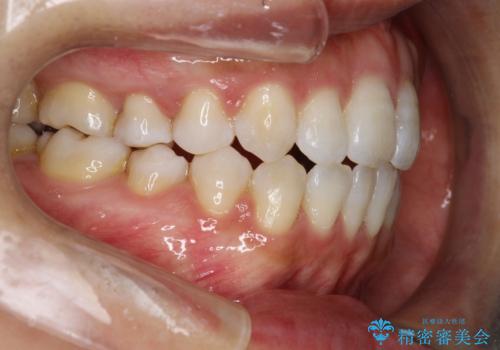

前歯がガタガタで咬めない ワイヤーによる抜歯矯正で整った歯並びへ

- 前歯がガタガタなのと、前歯でものが噛めないことを主訴に来院されました。

前歯の叢生があり、上下の前歯が接触していない開咬という状態でした。

左側の上下の前から4番目の歯を抜歯して、矯正することとしました。

ガタガタがなくなり、上下の前歯が接触すようになり、見た目とともに咬みやすくすることができました。